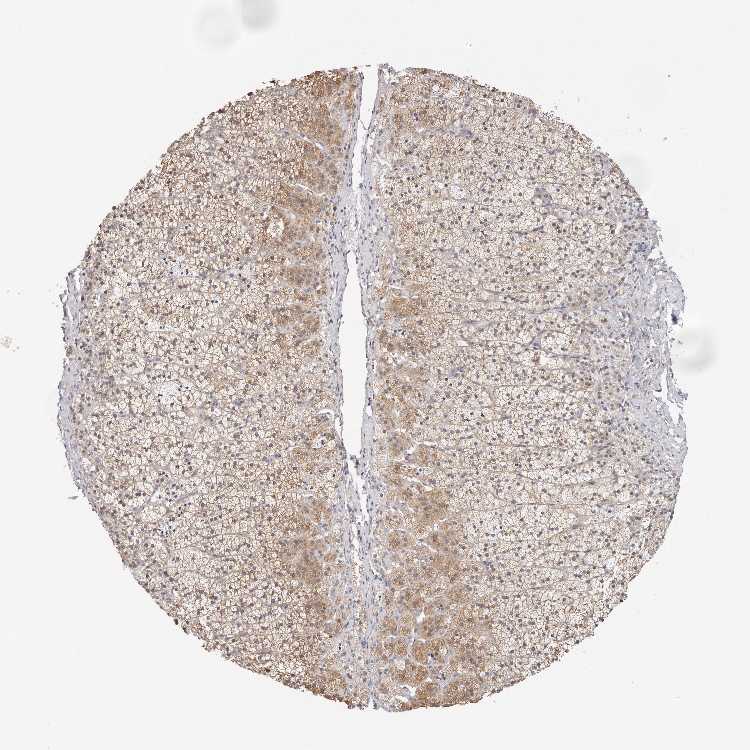

ADRENAL GLAND - Antibody stainingi

Antibody staining in the annotated cell types in the current human tissue is reported as not detected, low, medium, or high, based on conventional immunohistochemistry profiling in selected tissues. This score is based on the combination of the staining intensity and fraction of stained cells.

Each image is clickable and will lead to virtual microscopy that enables deeper exploration of all samples and also displays staining intensity scores, fraction scores and subcellular localization as well as patient and tissue information for each sample.

Antibody HPA030212Antibody HPA030213Antibody HPA030214Antibody HPA030215Antibody CAB013496

Glandular cells MediumLowMediumHighNot detected